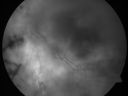

OS: Vertical C/D ratio is 0.5. The retina is white all surrounding the optic nerve 360° and from the macula out to the periphery.

PHOTOGRAPHS: Photos confirm clinical findings.